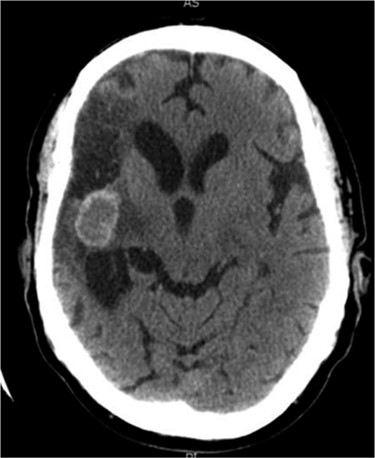

Between 2005 and 2012, the clinical condition remained stable and there were no significant radiological changes identified (Fig. 2). In July 2012, the patient re-presented with worsening left sided weakness and a left sided homonymous hemianopia. CT scan at this time demonstrated a 4 × 4cm well-defined mass of CSF density in addition to the pre-existing lesion in the right external capsule. Neither enhanced with contrast and there was no significant midline shift. An MRI head showed the lesion to contain a significant solid component. It appeared somewhat vascular and there was suspicion that it could represent a low-grade tumour (Fig. 3). The patient underwent a right-sided craniotomy to remove the mass.

Axial CT head (2007) demonstrating hyper-dense cystic abnormality in the right external capsule.